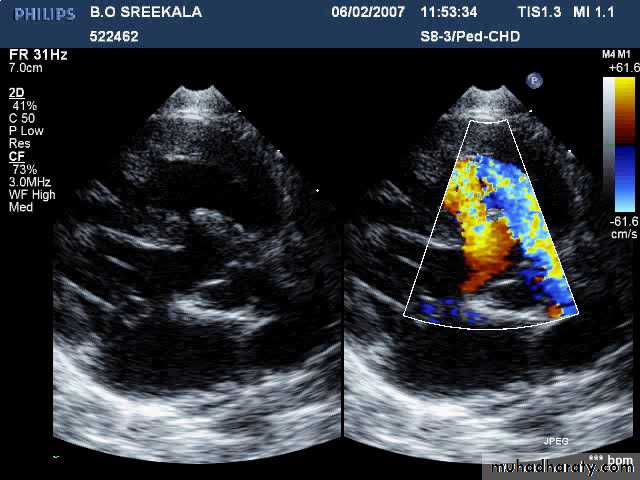

ATRIAL SEPTAL DEFECT (CONT.):

• Echo:• Trans-thoracic & trans-esophageal echocardiography is essential for Dx.

12/31/2015

Large Secundum ASD